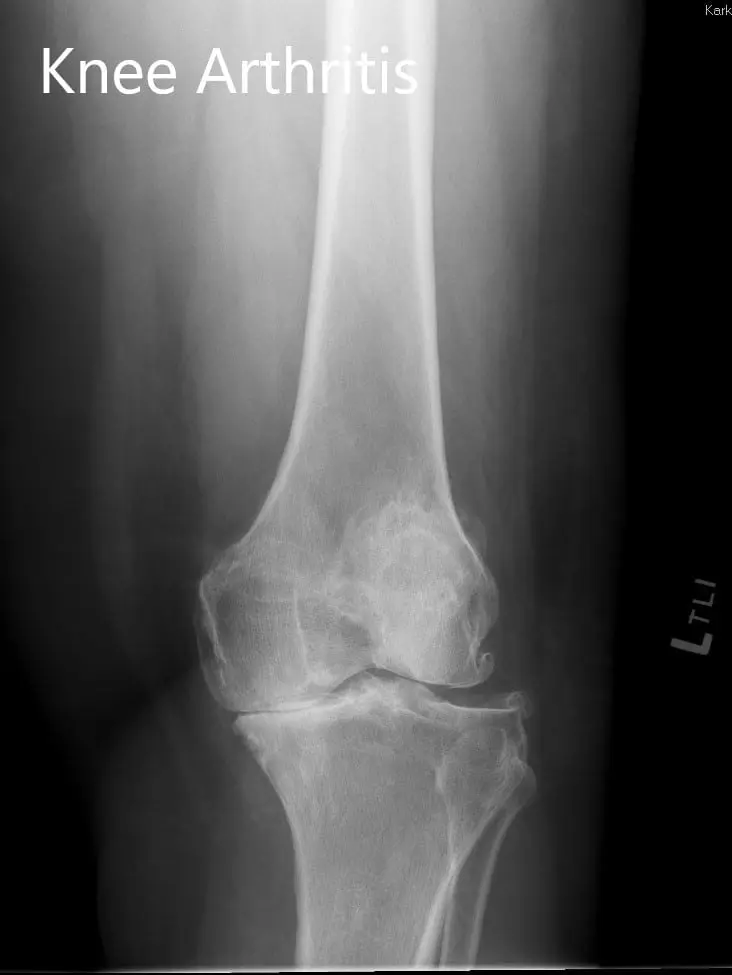

Imaging revealed severe tricompartmental osteoarthritis of the left knee with obliteration of the medial joint space and copious osteophyte.

Preoperative X-ray showing the lateral and the AP views